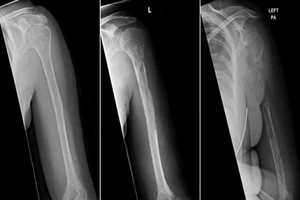

Người phụ nữ mắc bệnh cực hiếm, thế giới chỉ có 64 ca